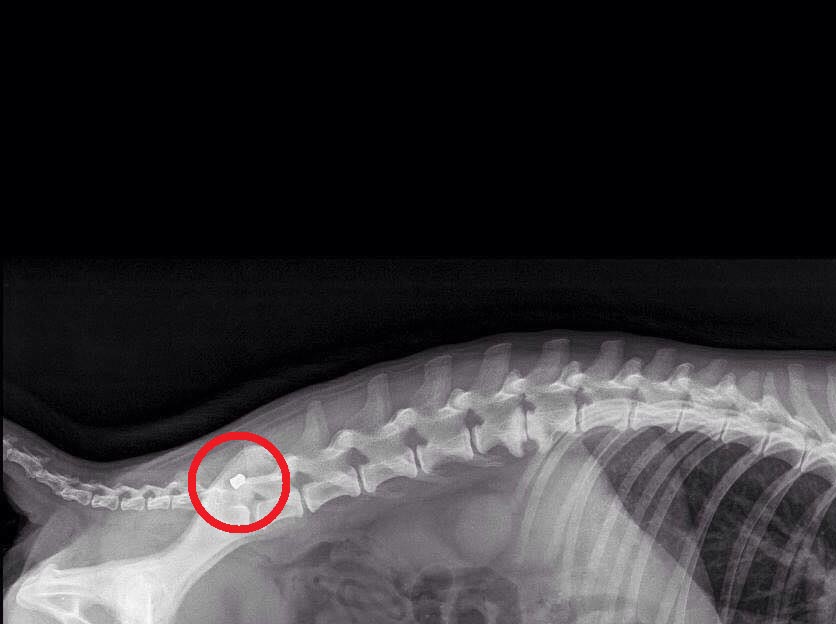

Στο κτηνιατρείο της Παναγιώτας Τσάγκου στα Λεχαινά νοσηλεύεται ο σκύλος ο οποίος εντοπίστηκε χθες στην περιοχή Συκιά κοντά στο λιμάνι στο Κατάκολο της Ηλείας. Το ζώο όπως εξήγησε στο www.zoosos.gr η Αργυρώ Χριστοδουλάκη το βρήκε να περπατάει εξαιρετικά περίεργα,  με μεγάλη δυσκολία κάπως λοξά και όπως φάνηκε τελικά από τις ακτινογραφίες είχε πυροβοληθεί με αεροβόλο στη λεκάνη.

KatakoloIliasPyrovolimenosAerovoloSkylosAktinografia 2Η ακτινογραφία έδειξε το σφαιρίδιο στη λεκάνη του ζώου.

Η κα Χριστοδουλάκη κατάφερε να το πιάσει μετά από πολλές προσπάθειες καθώς το ζώο ήταν εξαιρετικά φοβισμένο και το μετέφερε στο κτηνιατρείο. Η κα Τσάγκου εξήγησε στο www.zoosos.gr ότι τις επόμενες μέρες θα φανεί αν πρέπει να αφαιρεθεί το σφαιρίδιο ή όχι και αν η ζημιά που έχει κάνει στο ζώο, στη βάδιση του είναι αναστρέψιμη.